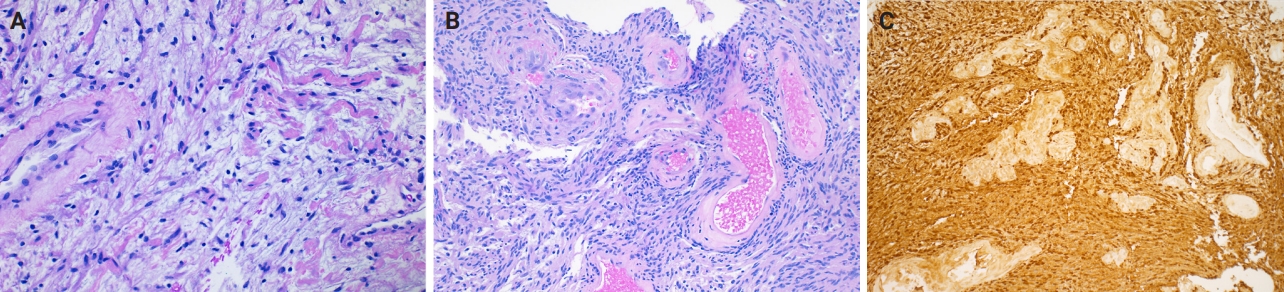

- Microscopically, breast schwannomas are well-circumscribed or encapsulated and can have prominent nodularity (Fig. 3A). Classic schwannomas have a bland spindle cell proliferation with various degrees of anisonucleosis, and wavy, elongated nuclei with tapering ends. These are arranged in parallel rows (nuclear palisading), also known as Verocay bodies (Fig. 3B). There is an abrupt transition between hypercellular (Antoni A) and hypocellular areas (Antoni B) (Fig. 3C). Antoni B areas have loose and myxoid stroma (Fig. 4A). Other key features to schwannomas include numerous small to medium sized vessels with prominent hyalinization and thrombi inside the lumen (Fig. 4B) and may also contain areas of hemorrhage or hemosiderin deposition [3,19].

- Immunohistochemistry is often needed to diagnose schwannomas, especially with small core tissue samples in the breast. The two most important positive stains are S100 (Fig. 4C) and SOX10, which are strong and diffuse in Schwann cells [3]. Schwannomas can also be positive for CD34 (weak, variable), calretinin, CD56, CD68 [21], podoplanin and Type IV collagen [22]. Classically, these are negative for estrogen receptor (ER), progesterone receptor, human epidermal growth factor receptor 2, smooth muscle markers (smooth muscle actin, desmin) and epithelial membrane antigen (capsule/perineurium only) [3]. Cytokeratins are generally negative, but may have rare labeling [23].

Fig. 4.Core biopsy of breast schwannoma with myxoid loose stroma (A), variably sized hyalinized vessels with intraluminal fibrin thrombi (B) and diffuse nuclear and cytoplasmic S100 reactivity in lesional Schwann cells (S100 immunohistochemistry) (C).